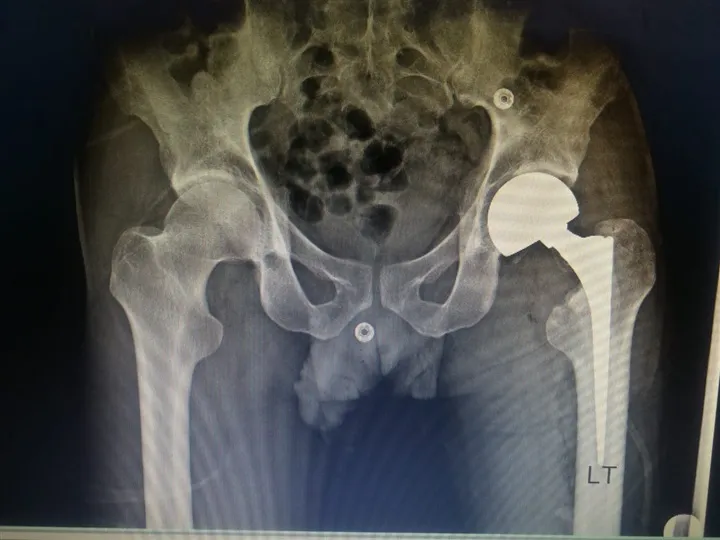

أعلنت الهيئة العامة للرعاية الصحية، عن نجاح أول عملية استئصال لأورام العظام تحت مظلة التأمين الصحي الشامل لشاب يبلغ من العمر 38 عامًا بمستشفى التضامن التابعة لهيئة الرعاية الصحية ببورسعيد.

وأشارت الهيئة إلى تمكن الفريق الطبي بمستشفى التضامن بورسعيد من إجراء العملية للمريض، حيث أنه يعاني من ورم سرطاني بالرئة مع وجود ثانويات بالمخ وكسر مرضي بعنق عظمة الفخذ اليسرى، وعليه تم استئصال الثانويات بعنق عظمة الفخذ مع كحت التجويف الداخلي لعظمة الفخذ اليسرى، مع استعواض مفصل الفخذ بنصف مفصل ثنائي القطبين اسمنتي مع ملئ القناة والتجويف العظمي لعظمة الفخذ بالاسمنت الطبي، وتمت العملية بنجاح.